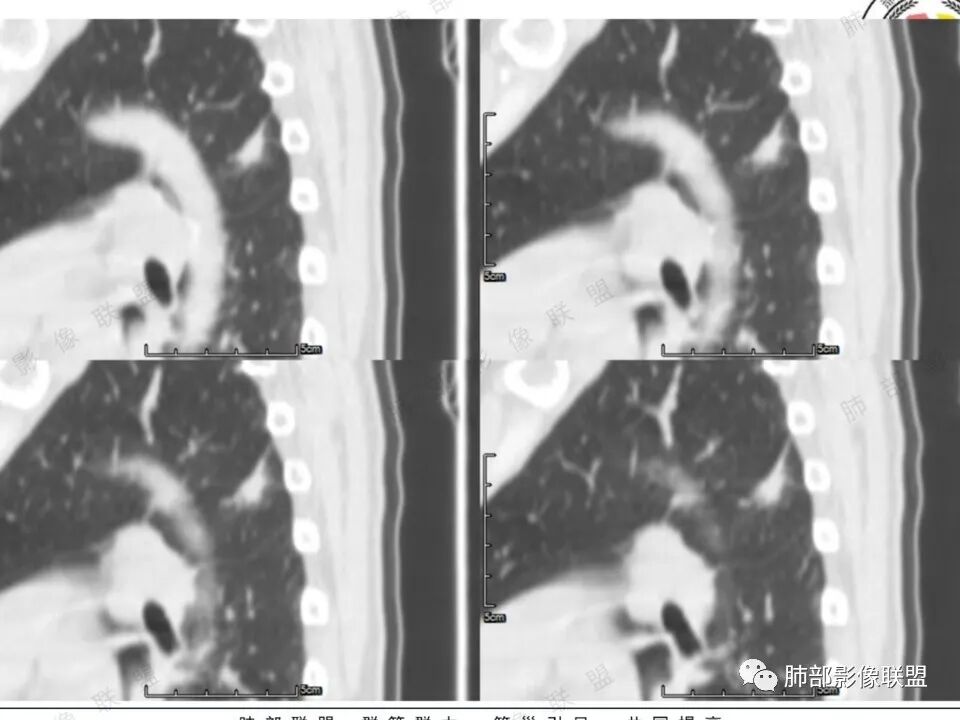

女,41岁,体检发现肺部结节。左肺上叶长形病灶,具有轻度膨胧感,刀切尖角征,胸膜粘连,早期强化见薄环强化征象,后期有延迟强化特点。病灶周围不是很干净。考虑结核肉芽肿或炎症肉芽肿。

患者中年女性,体检发现。胸部CT:左肺上叶后段长条形结节灶,边缘光滑,边界清楚,见分叶、毛刺、胸膜牵拉及平直征象。增强明显强化,内可见血管增粗,综合考虑恶性病变,浸润性腺癌可能大,鉴别结核。

秦化君:

晨读反思:1.边缘磨玻璃还是比较清楚;2.有收缩力;3.强化明显提示内部有血管,说明破坏力不强。

1.中年女性,体检发现;2.左肺上叶后段长条形结节灶,边缘有膨隆,也有收缩,腺癌和炎性结节都可以,但是周围见边界清楚磨玻璃影强烈提示腺癌可能性。3.显著强化的肺结节,无论如何都应当引起我们的高度重视!尽管炎性病灶和新生物都可以,尽管强化程度不能作为诊断癌肿的依据。

4.本例结节强化程度明显低于主动脉,也缺乏血管畸形的典型的迂曲结构,血管畸形可能性不大。

★存在边界清楚的磨玻璃影,常常提示腺癌的可能性,尤其随诊复查没有变化。